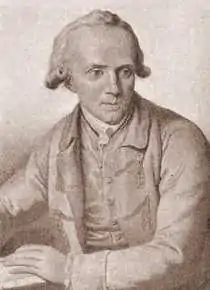

Samuel Auguste Tissot, lui, avait élaboré une théorie « médicale » à partir d’hypothèses de plusieurs médecins de l’époque, dont le célèbre Herman Boerhaave, et surtout du livre Onania[73].

« Tissot suggéra que le sperme jouait un rôle important dans le fonctionnement normal de l’organisme, et que le gaspillage de ce liquide par des activités sexuelles pouvait affaiblir l’organisme et provoquer des maladies. Ce liquide vital devait être « dépensé » parcimonieusement, et seulement lorsqu’il y avait une chance raisonnable de procréer. À partir de cette théorie, des médecins […] élaborèrent un répertoire des maladies liées au gaspillage du sperme dans des activités sexuelles dommageables, dont la masturbation[5]. »

« C’est, en grande partie, au médecin suisse S. Tissot (1728-1797) que l’on doit une conception aussi négative de la masturbation ; il fit de ce sujet un thème scientifique, et transforma la masturbation, considérée jusque-là comme un simple péché, en une maladie qu’il fallait soigner. Tissot croyait que toute activité sexuelle était dangereuse, parce qu’elle refoulait le sang vers la tête, n’en laissant plus assez dans le reste du corps, ce qui provoquait la dégénérescence des nerfs et autres tissus vitaux. En accord avec les connaissances scientifiques de l’époque, il était certain que cette forme de détérioration nerveuse était cause de la folie. Tissot était convaincu que la masturbation était une forme de sexualité particulièrement “dangereuse”, parce qu’elle était commode, qu’elle pouvait commencer pendant les années vulnérables de l’enfance, et parce que le sentiment de culpabilité éprouvé par celui qui se masturbe, eu égard à son péché, irritait son système nerveux et le rendait plus fragile. Les parents cherchèrent désespérément à écarter leurs enfants de ce fléau. Les médecins étaient contents de leur rendre ce service ; après tout, c’était du devoir du médecin consciencieux de mettre fin à la masturbation[29]. »

Le livre de Tissot L’Onanisme, traité sur les maladies produites par la masturbation eut un très grand succès avec soixante-trois éditions entre 1760 et 1905. Tissot y expose les maladies provoquées par l’autostimulation.

« Je me suis proposé d’écrire sur les maladies produites par la masturbation, et non pas du crime de la masturbation : n’est-ce pas d’ailleurs assez en prouver le crime que de démontrer qu’elle est un acte de suicide ? … J’ai vu un jeune homme atteint d’épuisement dorsal. Il était d’une fort jolie figure et, malgré le fait qu’on l’ait souvent averti de ne pas se livrer au plaisir, il s’y livra néanmoins et devint difforme avant sa mort… Le cerveau même, dans ce cas, paraissait s’être consumé. En effet, les malades deviennent stupides et si raides que je n’ai jamais vu une si grande immobilité du corps. Les yeux mêmes sont si hébétés qu’ils n’ont plus la capacité de voir… La peinture du danger, quand on s’est livré au mal, est peut-être le plus puissant motif de correction, c’est un tableau effrayant propre à faire reculer d’horreur. En voici les principaux trais : un dépérissement général de la machine ; l’affaiblissement de tous les sens corporels et de toutes les facultés de l’âme ; la perte de l’imagination et de la mémoire ; l’imbécillité, le mépris, la honte ; toutes les fonctions troublées, suspendues, douloureuses ; des maladies longues, bizarres, dégoûtantes ; des douleurs aiguës et toujours renaissantes ; tous les maux de la vieillesse dans l’âge de la force… le dégoût pour tous les plaisirs honnêtes, l’ennui, l’aversion des autres et de soi ; l’horreur de la vie, la crainte de devenir suicide d’un moment à l’autre ; l’angoisse pire que les douleurs ; les remords pires que l’angoisse… voilà l’esquisse du sort réservé à ceux qui se conduiront comme s’ils ne le craignaient pas[48]. »

À la fin du XVIIIe siècle, la renommée de Tissot était telle qu’il n’était plus possible pour un médecin de ne pas condamner l’autostimulation. La masturbation était devenue un problème médical « incontournable » et un problème social majeur[74].